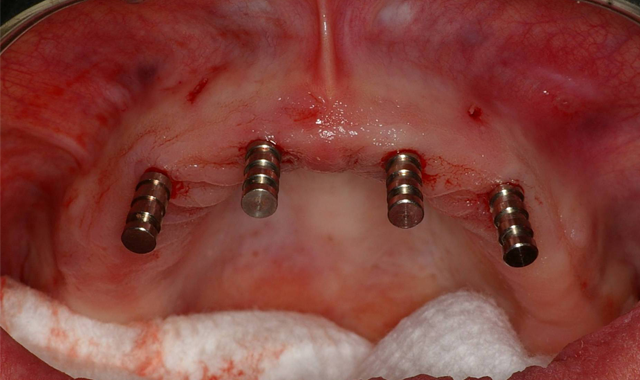

Fig. 5 Fig. 6

Using a rotary tissue punch (OCO Biomedical), an outline cut was created over the initial osteotomies and the tissue plugs were removed with a curette (Goldendent). Once the osteotomy sites were completed with sequential osteotomy formers, the dental implants were placed (Fig. 5) with the surgical handpiece at a speed of 25. The ratchet wrench was then connected in order to torque the dental implants to final depths reaching a torque level of about 25-30 Ncm.

A baseline ISQ reading was taken of these implants utilizing the Penguin RFA (Aseptico). Since the initial readings were all above 70, 3 mm height LOCATOR attachments (ZEST Dental Solutions) were tightened into the dental implants (Fig. 6).